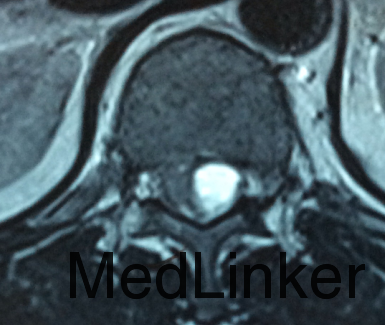

主诉:左下肢麻痛半年,加重伴乏力2周。 病史:患者半年前无明显诱因出现左下肢麻痛,腰部疼痛不明显,久站后有酸胀感。加重伴乏力2周;患者目前无二便失常。患者一般情况尚可。

体查:脊柱无明显畸形侧凸。各棘突及棘旁无明显压痛;左下肢肌力较右侧稍减弱,余四肢肌张力、感觉等无明显异常;双侧膝反射、踝反射无明显异常。病理征未引出。 辅助检查:三大常规、血生化检查未见明显异常,主要脊柱影像学检查如下,请参阅。

诊断:T12-L1椎管内肿物 治疗:患者入院后尽快完善相关检查,请神经外科会诊。经治疗组讨论,拟行“T12-L1椎管内肿物切除+钉棒内固定术”。

讨论:患者椎管内肿物,从影像学表现上看,主要考虑神经鞘瘤,但确诊需依靠手术的病理,同时根据患者的病理情况决定下一步治疗。